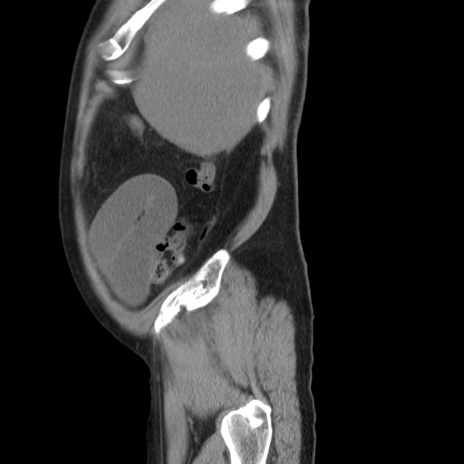

症例20(矢状断像)

【症例】 60歳代男性

【主訴】 腹部膨満、嘔吐

【現病歴】5日前頃より倦怠感を認め食事量減少し4日前の朝嘔吐、食事摂取困難となった。 3日前近医受診し点滴施行され整腸剤などを処方された。 当日他院を受診し、腹部膨満著明、炎症反応の上昇(CRP10.8、WBC11200)あり、紹介受診となる。

【身体所見】 意識JCS1 受け答えがはっきりしないBP 111/57mHg、 P 67bpm、、BT35.2°C、SpO2 97%(RA)、 腹部:膨隆、打診で鼓音あり、全体的に圧痛有り、腸蠕動音(-)、反跳痛ははっきりせず。

【データ】WBC 11400、CRP 14.20